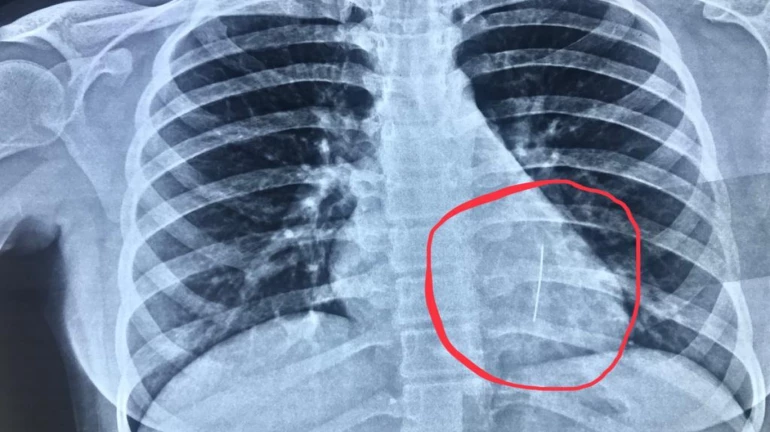

21 नवंबर को इनाया गोवा घूमने के लिए गई थी। तभी वहां पर स्कार्फ पहनते वक्त उसने पिन मुह में रख ली और वह पिन गलती से निगल गई। इनाया को लगे हाथ मेडिकल कॉलेज में एडमिट किया गया। पिन आखिर कहां फंसी है इसकी जानकारी पाने के लिए लड़की के सीने का एक्स-रे किया गया। साथ ही एण्डोस्कॉपी के द्वारा निकालने का प्रयास किया गया। लेकिन यह प्रयास असफल रहा।

जान मल्टिस्पेशॅलिटी हॉस्पिटल में डॉक्टरों द्वारा निकाले गए एक्स पे पचा चला कि यह जो पिन लंग्स में फंसी है, बहुत ही धारदार है। खासकर यह पिन पिछले 6 दिनों से लंग्स में फंसी थी। जिससे रक्त वाहिनियों को खतरा हो सकता था। जिसके चलते फोरसेप्स का उपयोग कर ब्रॉन्कोस्कोप द्वारा पिन को बाहर निकाला गया।